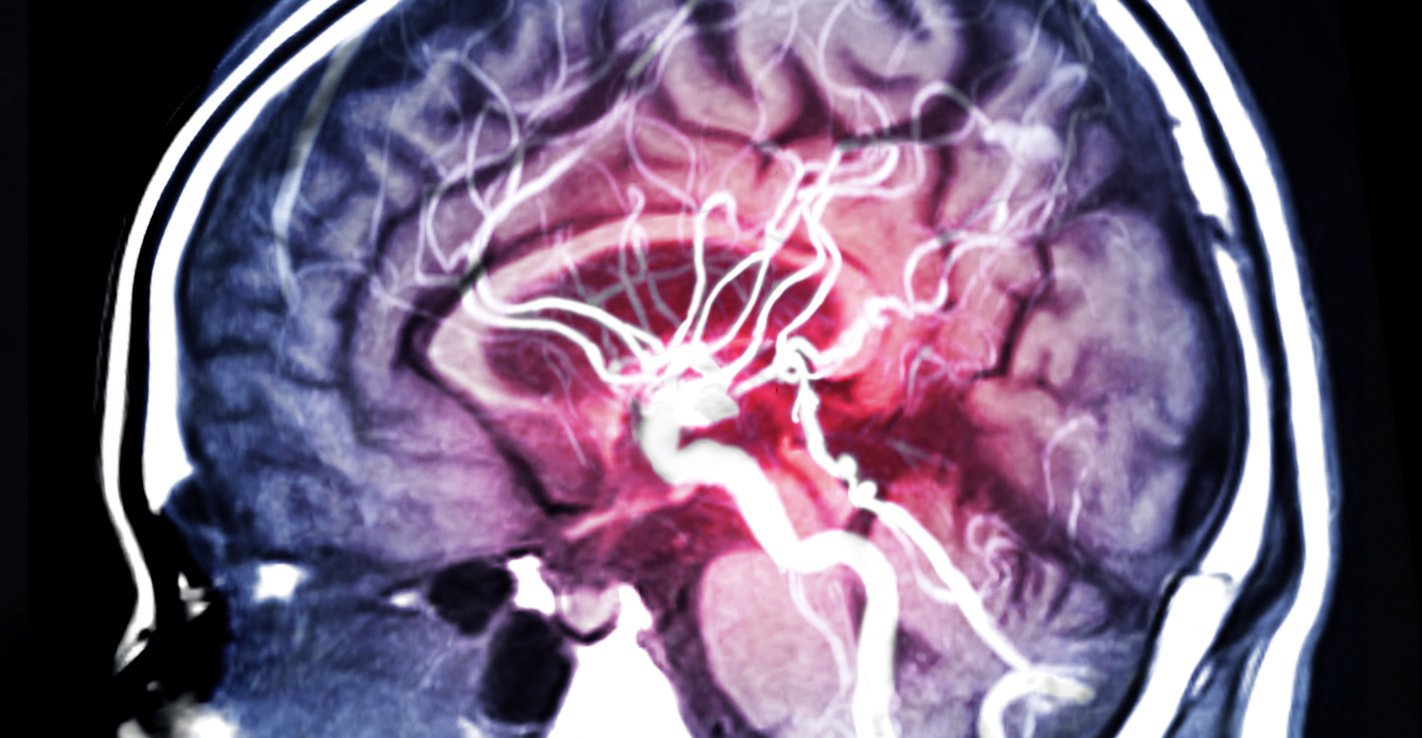

mra brain or magnetic resonance angiography (mri) of vessel in the brain sagittal view for evaluate them stenosis (abnormal narrowing), occlusions, aneurysms (vessel wall dilatations, at risk of rupture) or other abnormalities